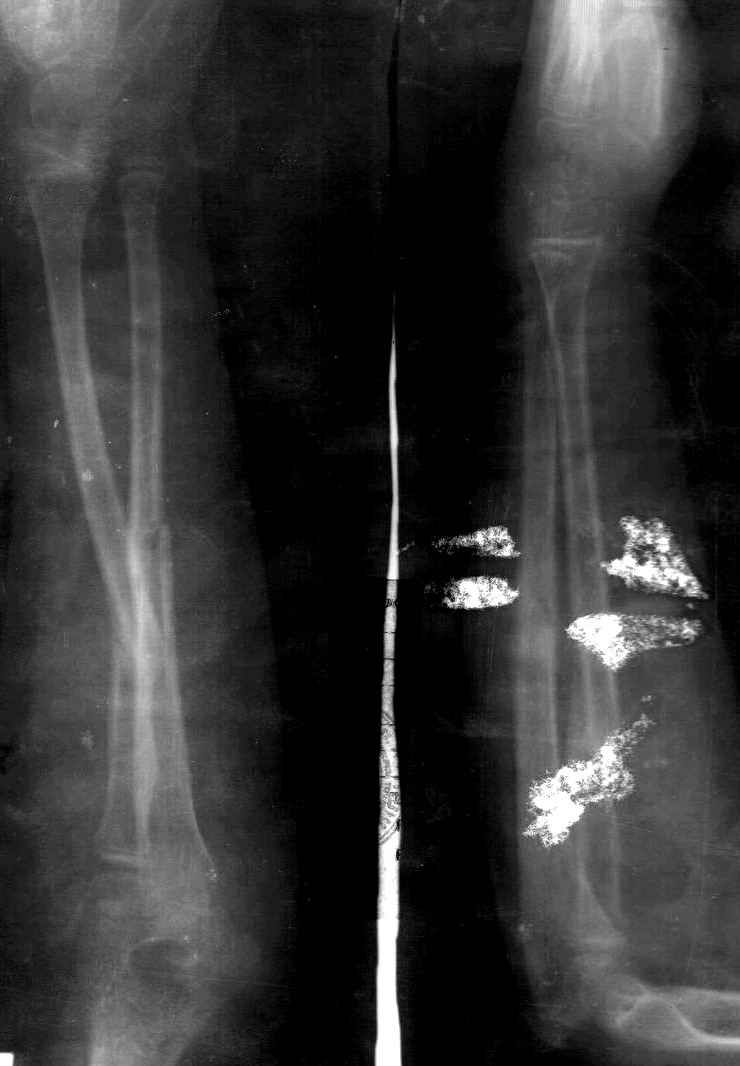

Позволю категорически не согласиться с высказанным мнением. Оставлять данную деформацию без коррекции нельзя, - ограничение ротационных движений будет только наростать. Остаточные угловые деформации костей предплечья у детей на уровне диафиза не устраняются самостоятельно. Данное стояние отломков (смещение под углом 35 гр.) и клиническаяя картина (боль и ограничение ротационных движений предплечья) - это абсолютное показание к устранению деформации. Каким способом это делать зависит от возможностей и опыта хирурга.

Сделал симметричные снимки с максимальной супинацией и пронацией при согнутом предплечье в 90 град. Объем ротационных движений 90-100 град.

Снимок один сделан с супинацией, второй - оба предплечья в одинаково нейтральном положении. то есть по этим снимкам объем ротационных движений не оценить. Снимко в двух проекциях лучше и делать в среднем положении между пронацией и супинацией, то есть обе проекции в однм и том же положении, когда линия, проходящая через шиловидные отростки, идет в плоскости головки. Прошу прощения за усложнение простых вещей.